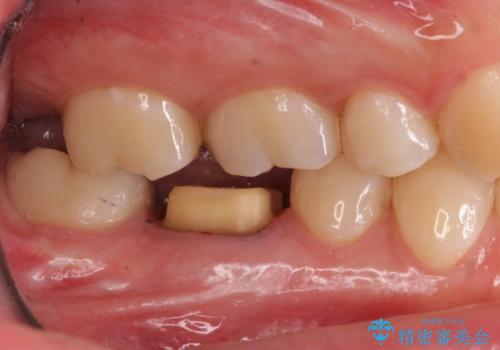

樹脂をセラミックにしたい ジルコニアクラウンでの治療

- 樹脂をやり替えたいとのことで来院されました。

特に大きな虫歯もありませんでしたが、残った歯が薄かったためクラウンでの修復処置を行いました。

- 右下6 仮歯+ジルコニアクラウン 11,000円+110,000円費用は治療当時の料金となります

インレーにすると残った歯が薄くなってしまう場合は術後の破折リスクが高いためクラウンで修復することがあります。